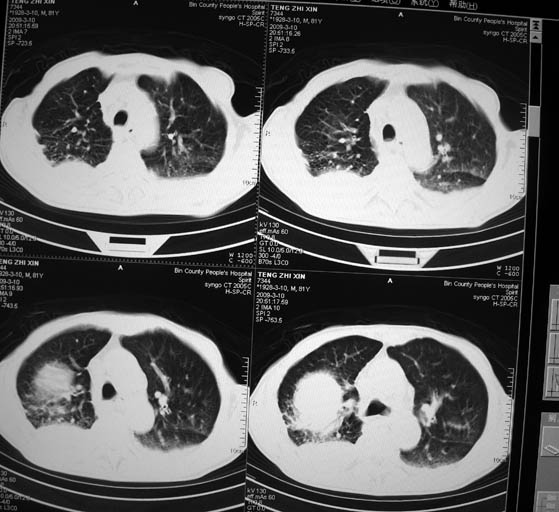

标题: CT18642:男,81岁,发热待查。

男,81岁,发热待查,右侧是占位还是膈疝?

1)考虑右肺下叶中央型肺癌并左肺转移。2)两肺上叶结核(陈旧性)。3)双侧胸腔积液。4)腹水。

右肺癌并双肺及胸膜转移。

右肺ca并肺对肺、胸膜转移。

右肺癌并双肺及胸膜转移

右中央型肺癌并双肺及胸膜转移